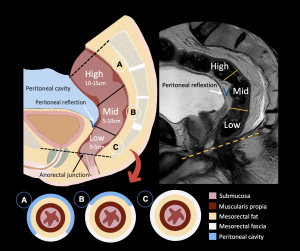

1. Rectal Anatomy on MRI

The rectum is divided according to its distance from the anorectal junction into low (0–5 cm), mid (5–10 cm), and high (10–15 cm).

MRI depicts the rectal wall layers, the surrounding tissues and the sphincter complex, all of which are critical landmarks for staging and surgical planning.